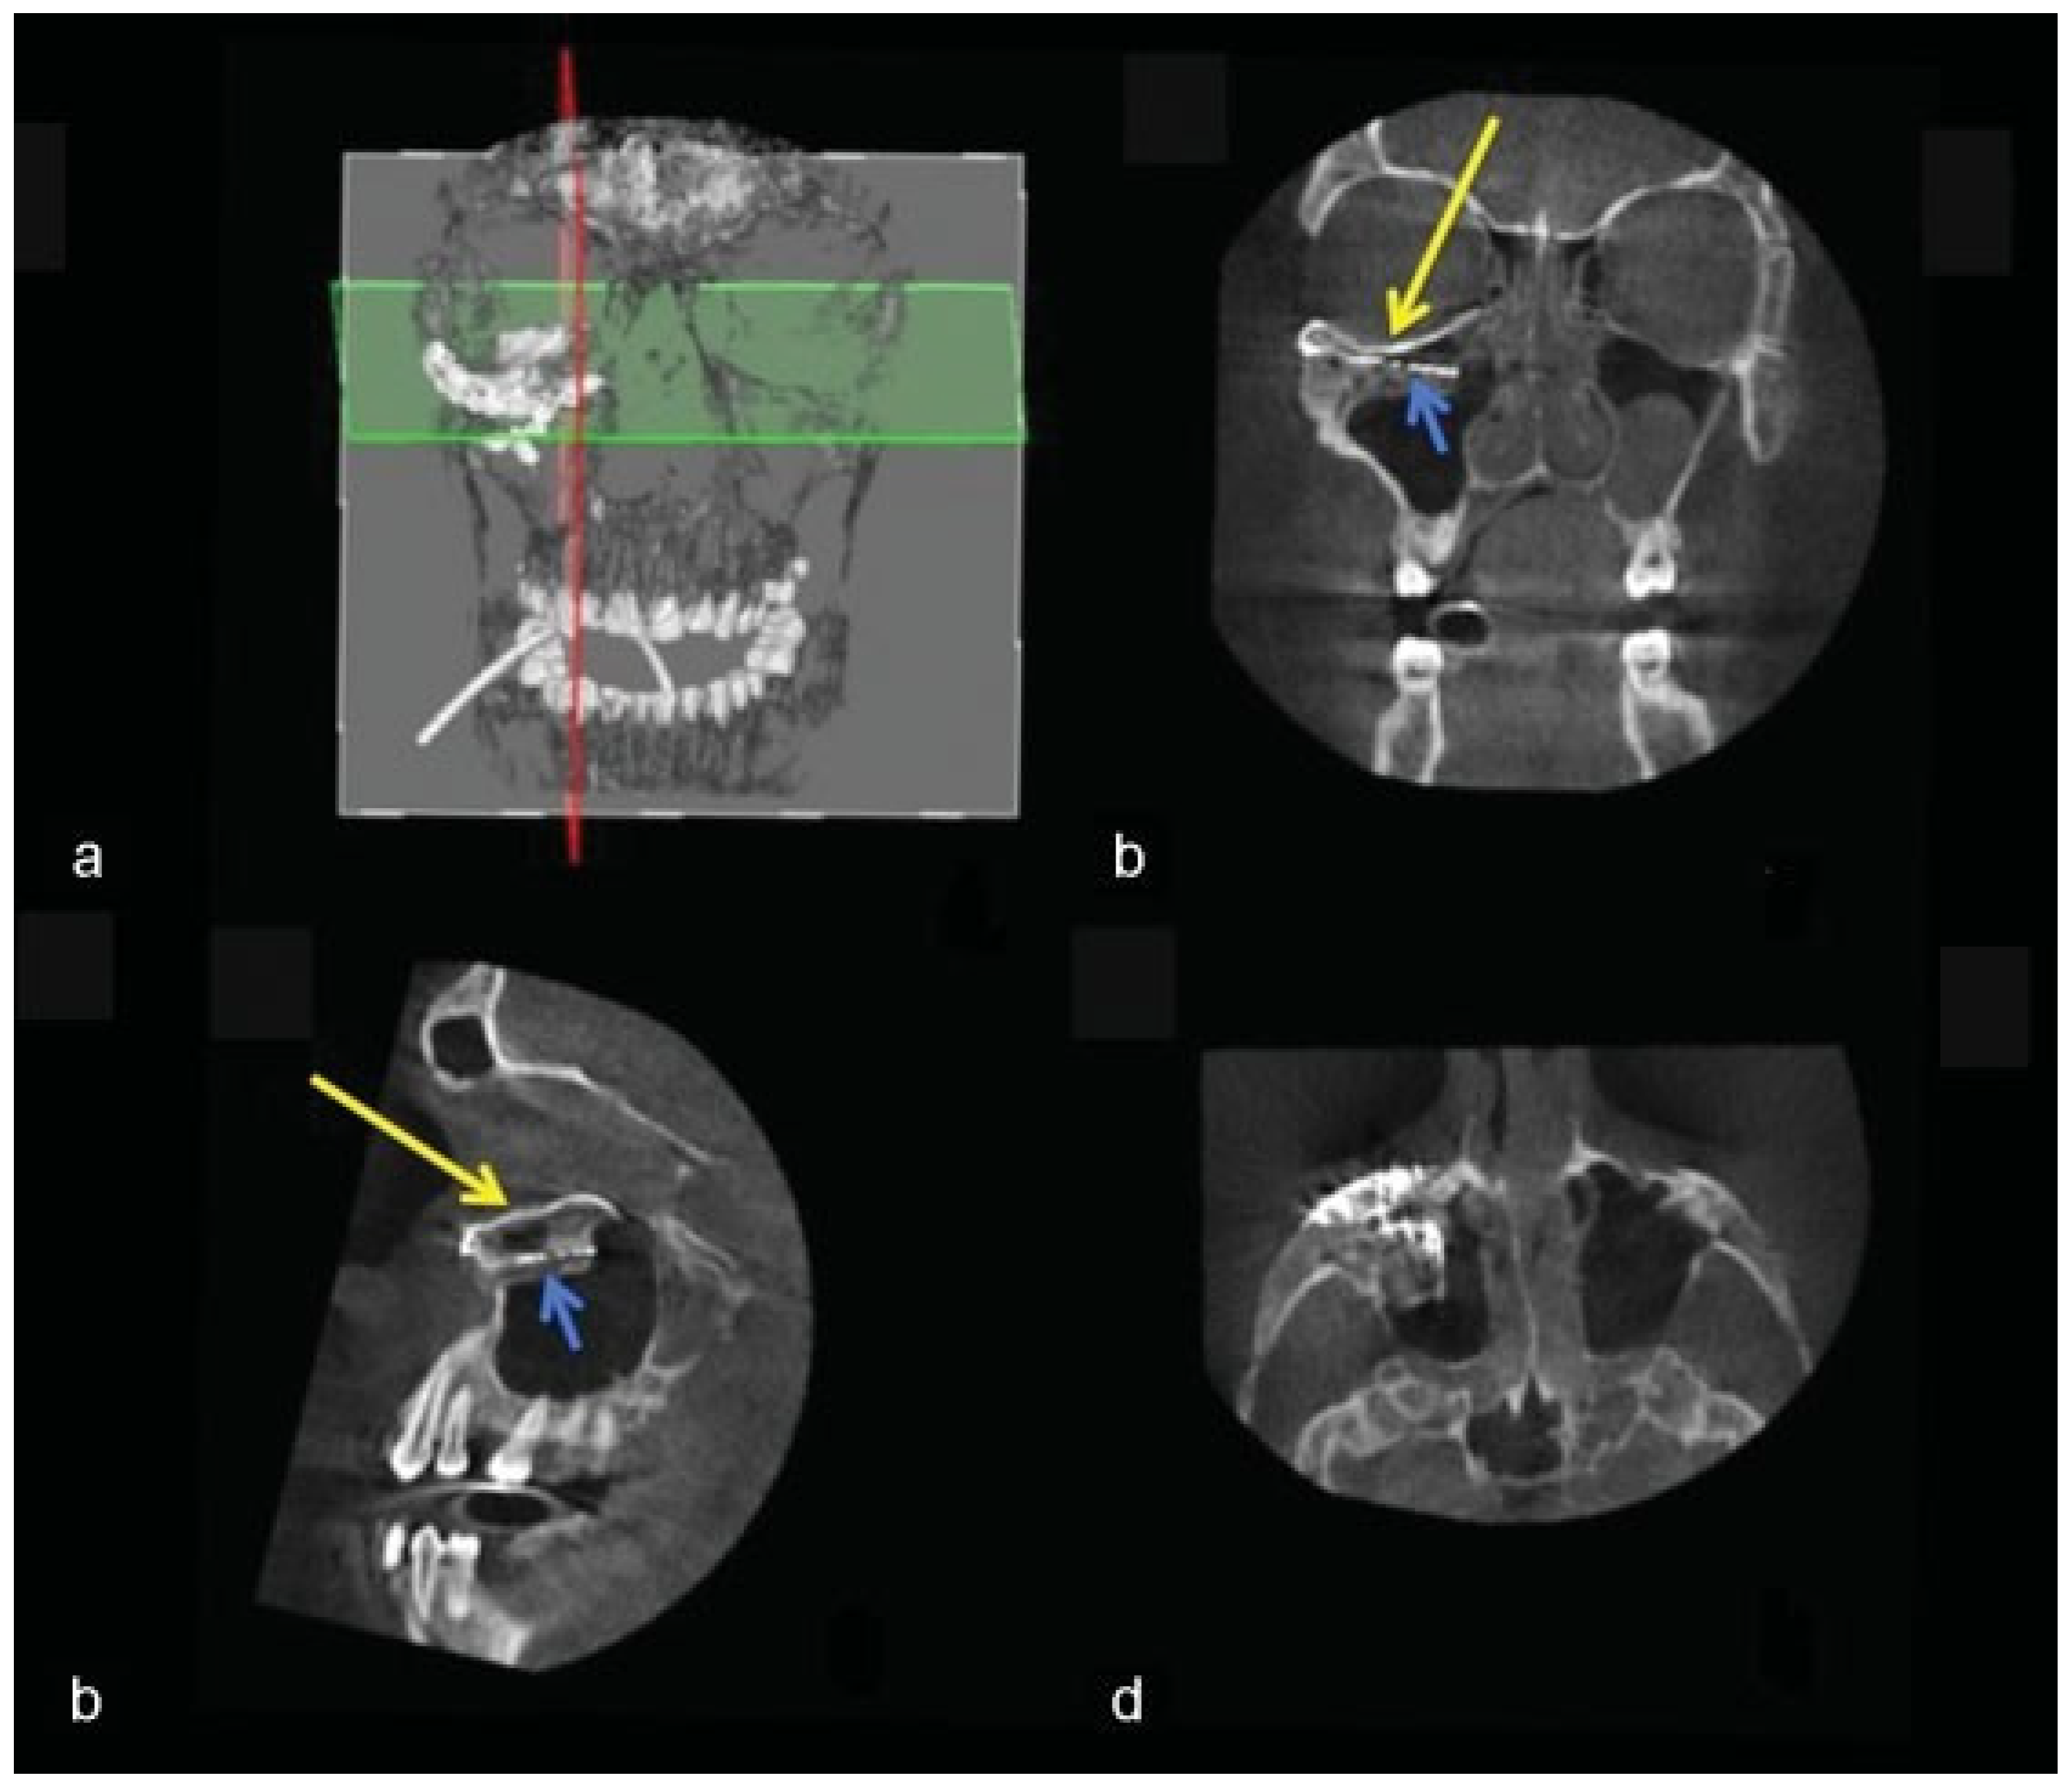

Figure 12. Case 3: Intraoperative 3D imaging using the Pulsera fluoroscopy system. (a) 3D reconstruction and section plane indication. (b) Good fit of the two puzzle pieces (long yellow arrow). Malpositioned mesh (short blue arrow). (c) Good fit of the medial puzzle-piece (long yellow arrow). The titanium mesh was not prebent and was 7 mm too low at the posterior sigmoid bulge (short blue arrow). (d) Axial view of the titanium mesh. The two-piece puzzle implants are visible only where they overlap the infraorbital rim.